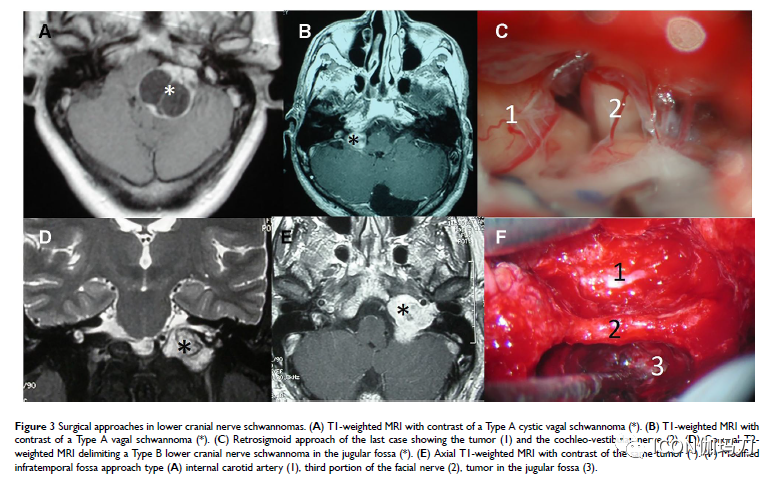

【综述】非前庭颅底和颅内神经鞘瘤的治疗趋势

图片尺寸779x480